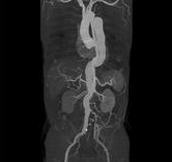

Body angiography with automatic bone and table removal - MIP reconstruction. Case: Aortic dissection. Left common iliac artery occlusion. Scanning: P0.83, 0.5s, 360mA, 100kV, weight 80kg, contrast 80cc